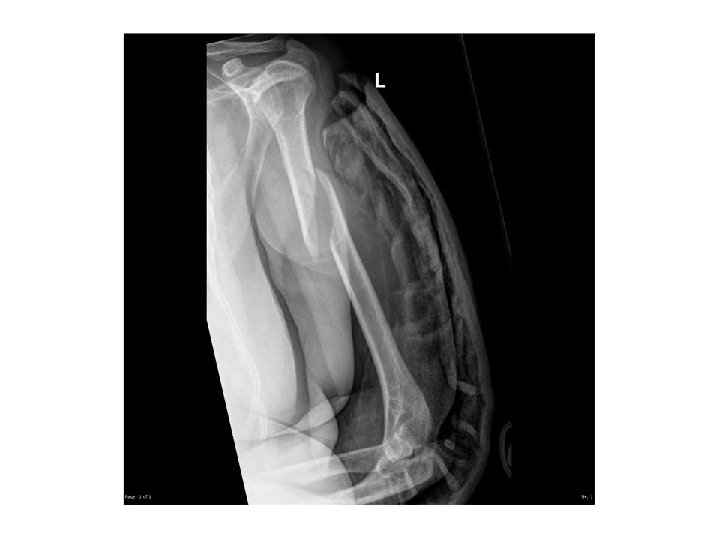

FOR EXAMPLE. . WHERE IS THIS LOCATED?

EXAMPLE… • This is a closed L distal femur fracture. • The main thing I want you to take from this example is the description of location